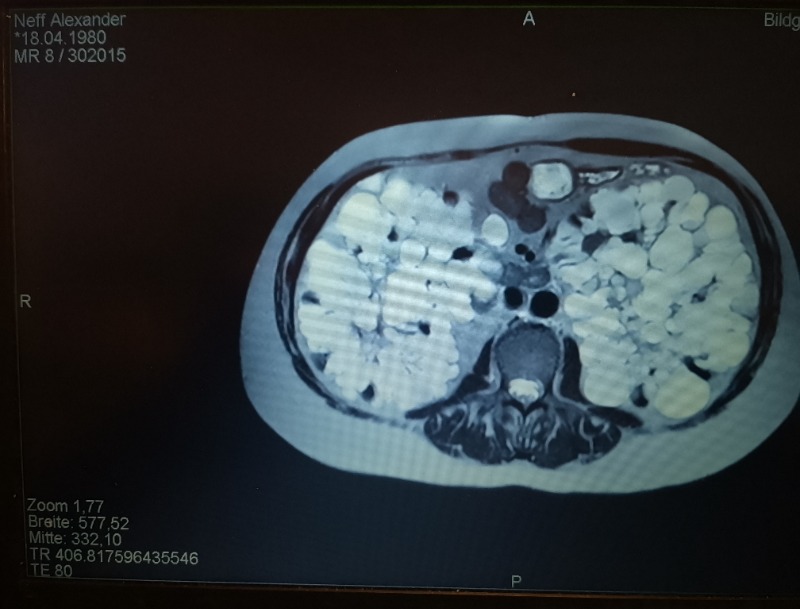

Suche Klink für beidseitige Nephrektomie meiner Zystennieren 20 Feb 2026 17:43 #528997